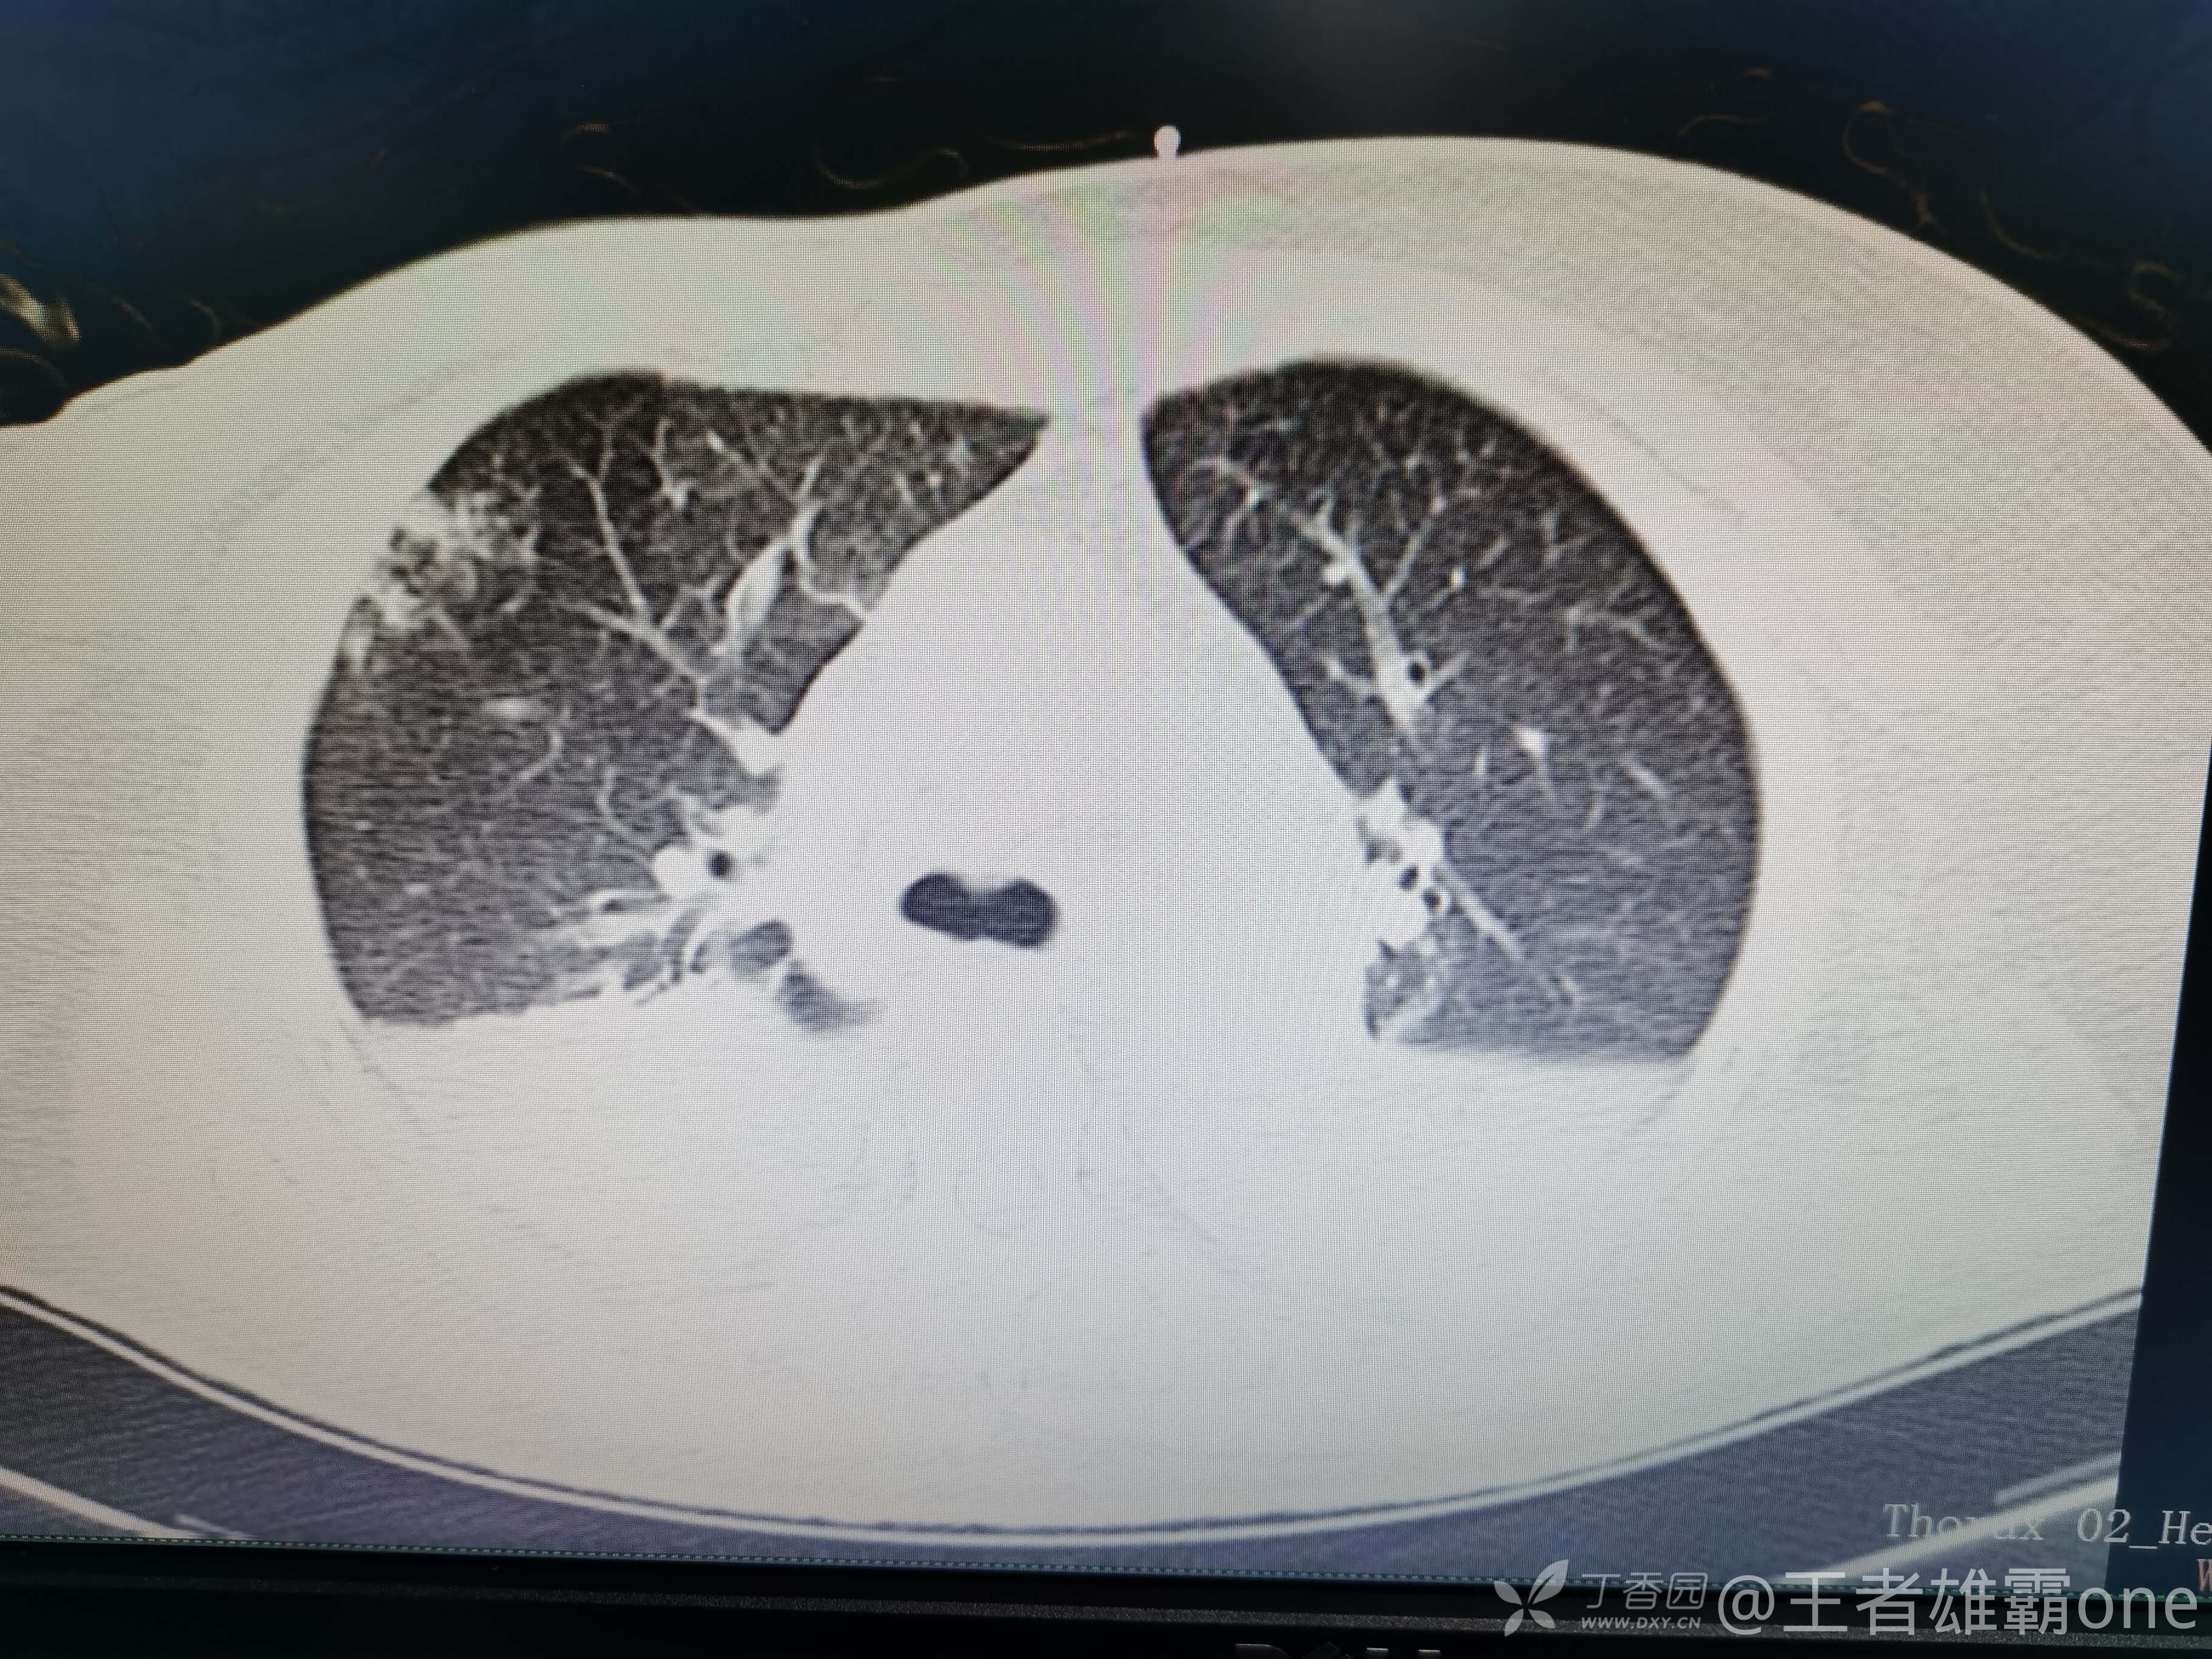

西门开心 推荐63岁女性,因车祸致短暂神志不清、多处疼痛4h入院。简单病史:伤后送至医院急诊就诊。完善头胸腹CT等检查,完善新冠核酸、血常规等化验。血常规提示血红蛋白62g/L。头颅CT提示未见明显外伤性改变。胸腹部CT视频见下:

5.肺挫伤

6.双侧多发肋骨骨折

12.双侧胸腔少量积液